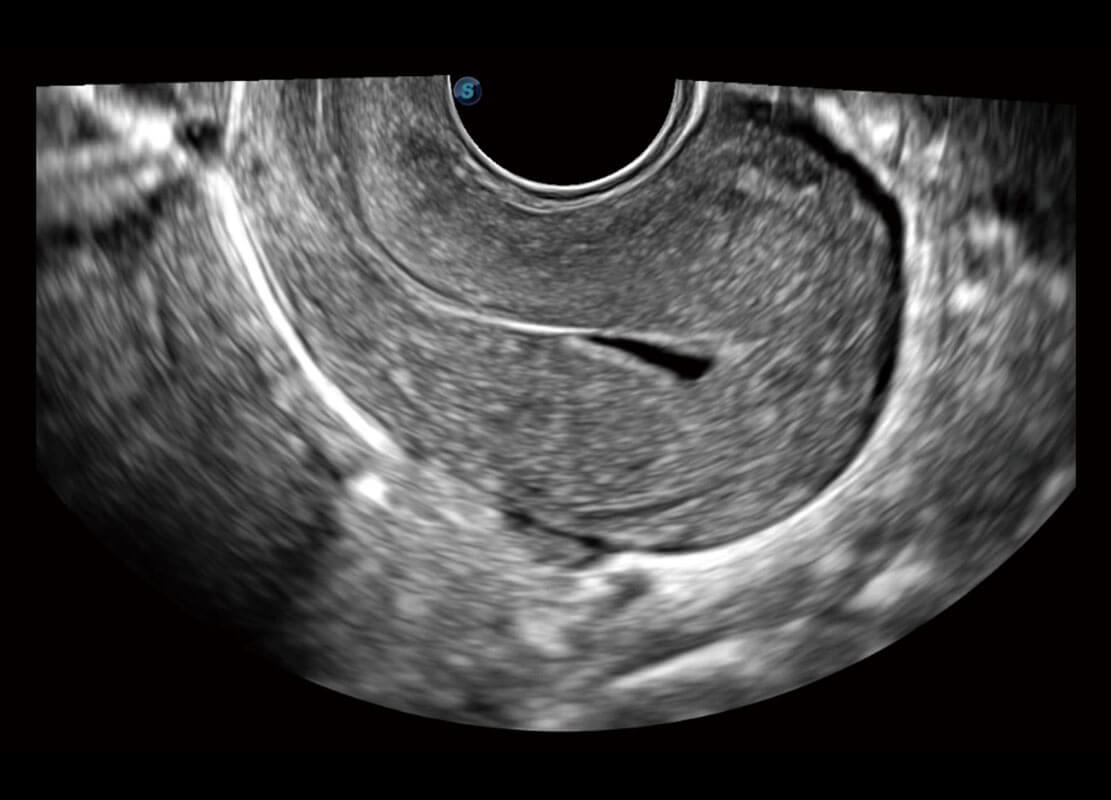

腔内妇科-宫腔分离

P60优异的图像质量搭载专科探头,在妇科基础疾病的诊断、卵泡生长的监测、输卵管通畅情况的判别等方面为您提供生殖应用方案。